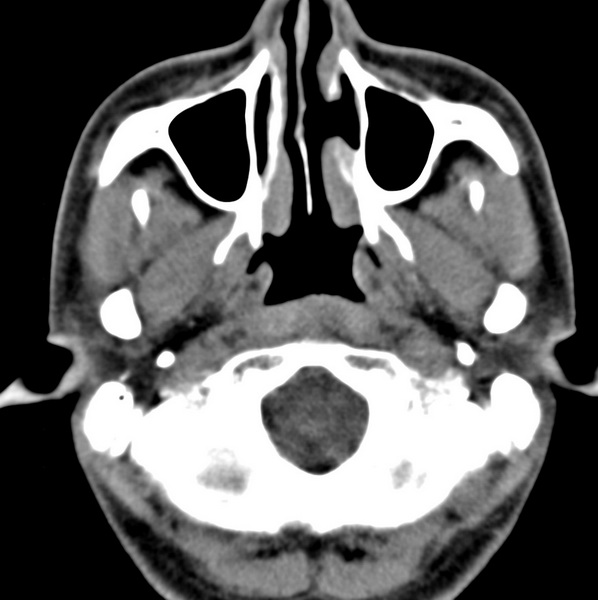

男、31、鼻咽部肿瘤放疗后请帮忙看看。

效果好,右侧破裂孔扩大,局部骨质缺损,为颅底骨质破坏。

1)鼻咽部肿瘤侵犯颅底放疗术后改变。2)左侧蝶窦炎。

咽后壁增厚,左侧咽鼓管隆突增大、咽鼓管咽口变浅,同侧咽旁间隙较窄。右侧颅底骨质破坏?为什么不在同一侧?

鼻咽部肿瘤侵犯颅底放疗术后改变.